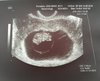

9ty tydzien, poszukam numeru i zadzwonieKtóry tc? Może zadzwoń do lekarza prowadzącego?